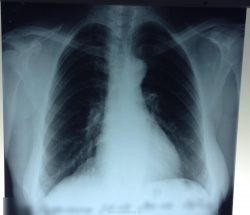

3. Липома легких. В органах дыхания жировики развиваются крайне редко, но если образование появилось там, у человека нарушается дренажная функция, и возрастают риски развития воспаления легких.